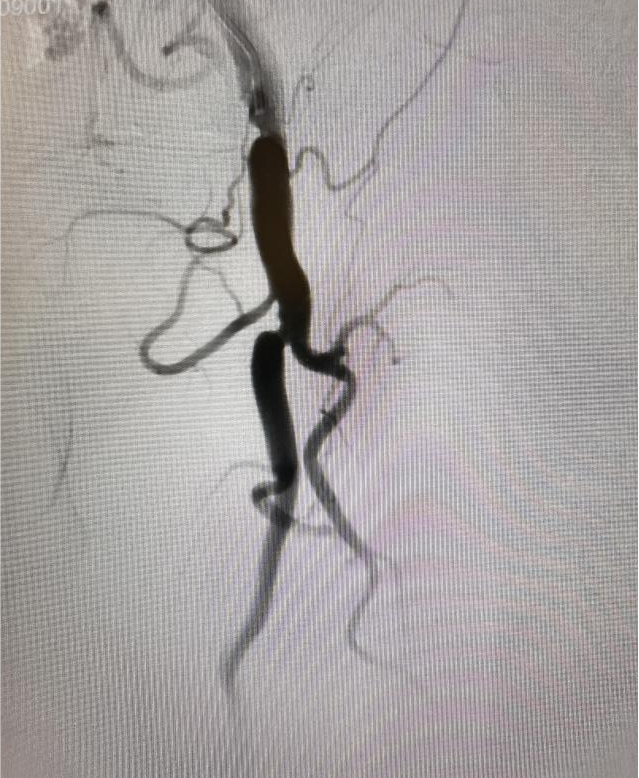

(图3:导丝逆向通过病变,到达正向单弯导管中)

面对这一技术挑战,刘超医生提出创新性解决方案:“正向不通,就尝试逆向突破。”在充分术前准备和严密风险评估基础上,手术团队果断采用逆行介入技术:于患者膝关节上方约2厘米处对股浅动脉远端进行精准穿刺,同步从近端与远端双向推进导丝。术中巧妙运用超滑导丝配合强支撑导管,实施“双向穿针引线”策略,最终成功实现导丝在闭塞段内的精准“会师”,逐步打通顽固性阻塞,恢复下肢动脉血流。术后患者下肢灌注明显改善,双下肢无力症状显著缓解,恢复情况良好,目前已可逐步开展康复训练。

(图4:闭塞导管开通成功,血流恢复)